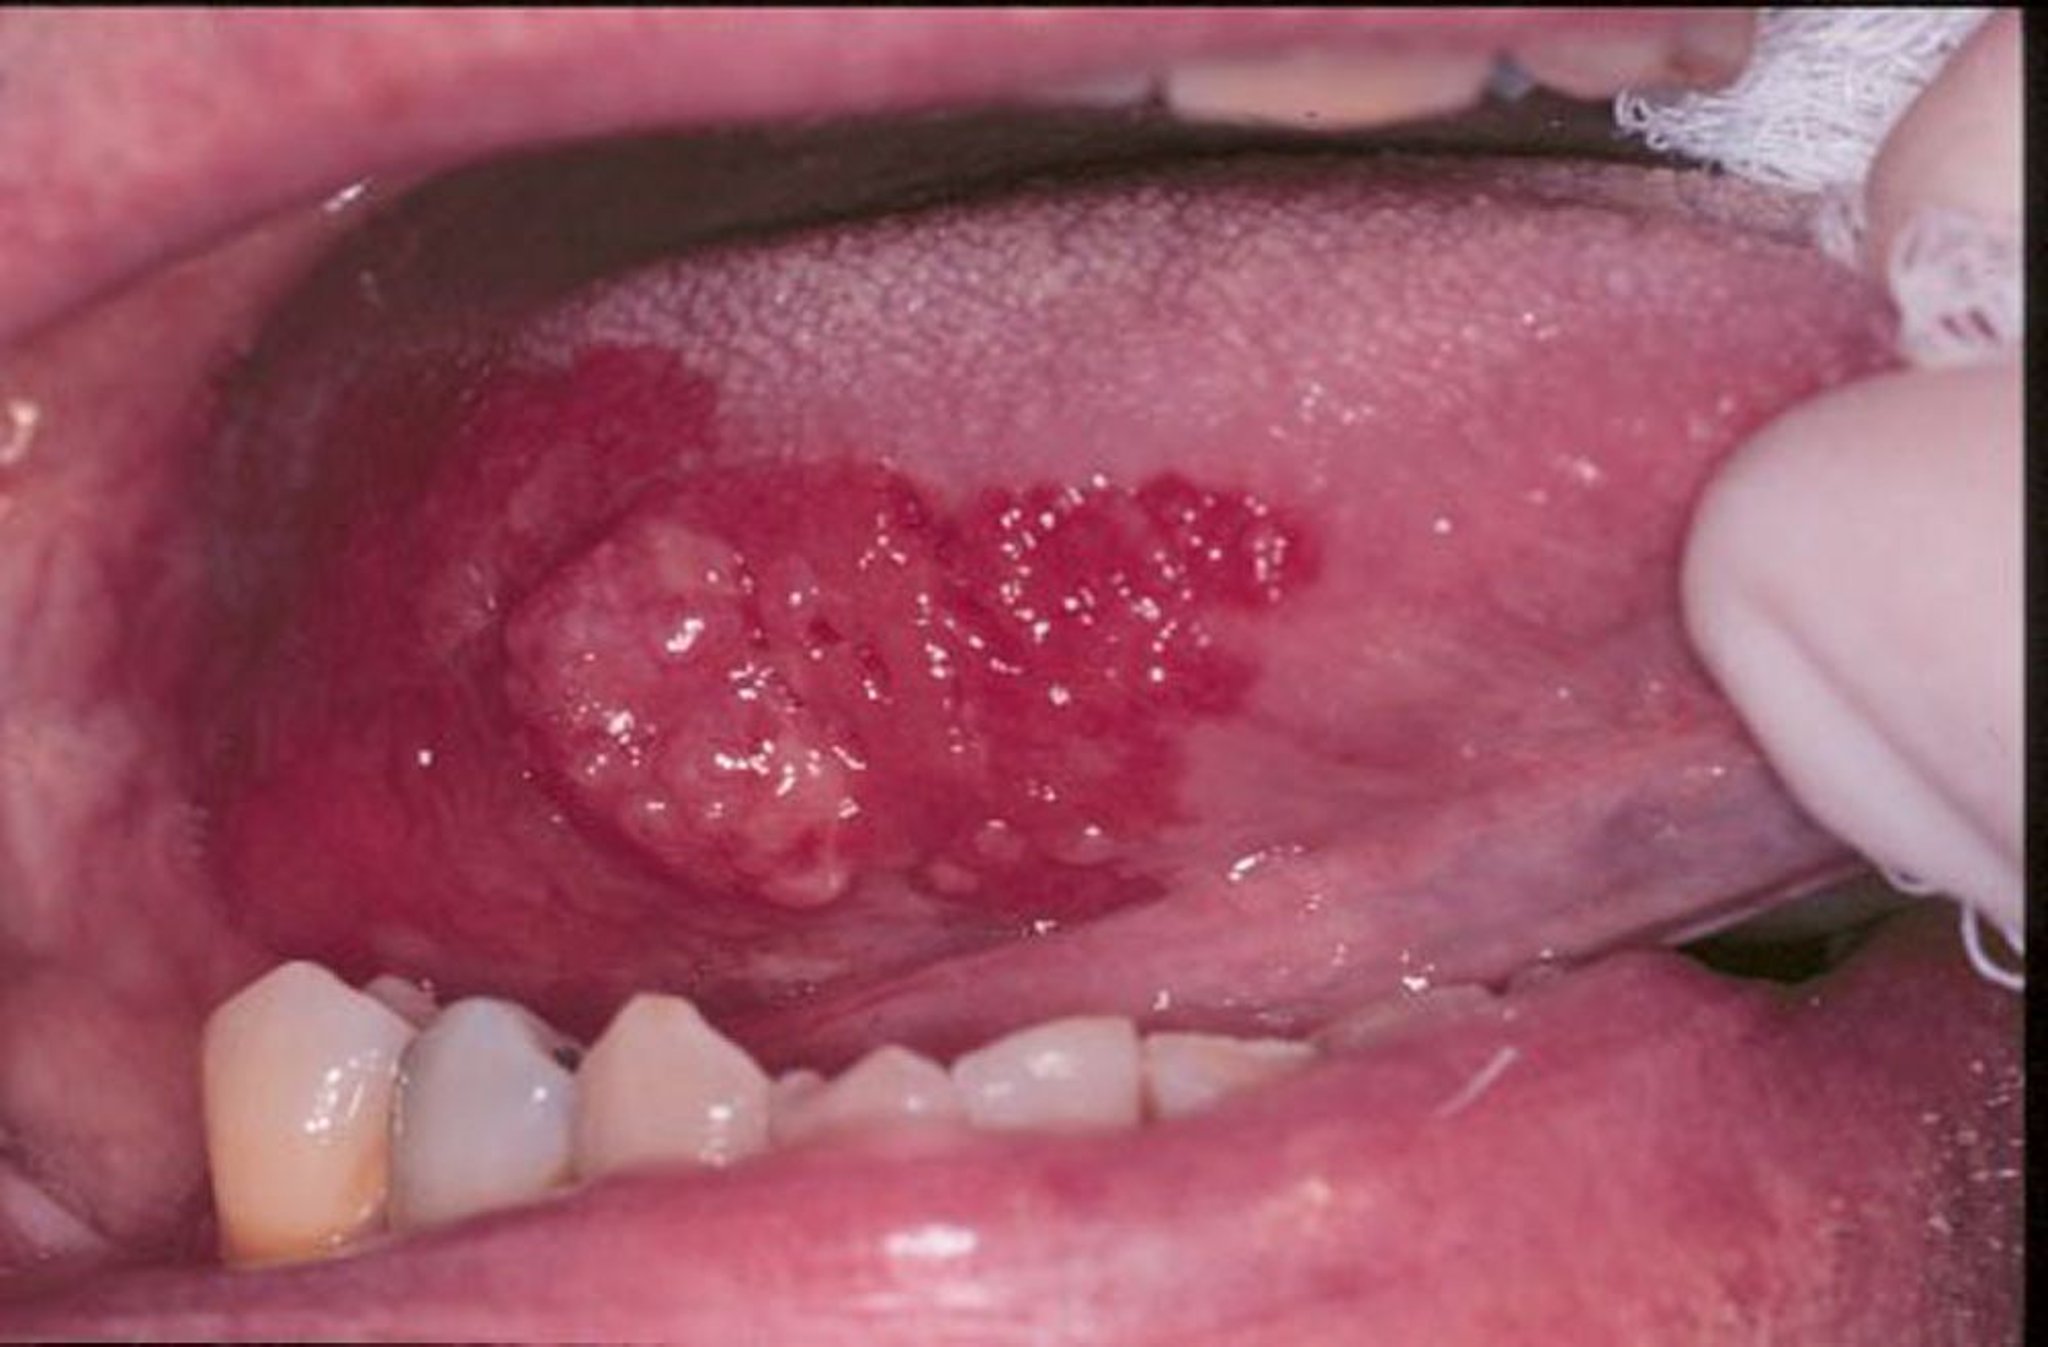

Érythroplasie et carcinome malpighien

L'érythroplasie est un terme général qui peut décrire des lésions rouges, plates ou érodées veloutées qui se développent dans la bouche. Dans cette image, un carcinome malpighien exophytique sur la langue est entouré d'une marge d'érythroplasie.

Image provided by Jonathan A. Ship, DMD.